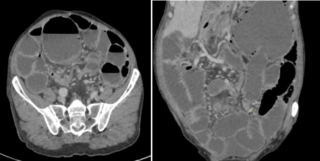

Figure 4 : Coupes scanographiques montrant une bride intestinale associée au volvulus cæcal.

Scanner abdominal (TDM) :

Le scanner a révélé une distension de l’intestin grêle située en amont de deux « signes du bec » (beak signs) contigus. Ce tableau clinique est compliqué par un volvulus du cæcum par torsion, avec la présence caractéristique d’une image en tourbillon (whorl sign), sans que des signes de complications majeures ne soient visibles à ce stade.